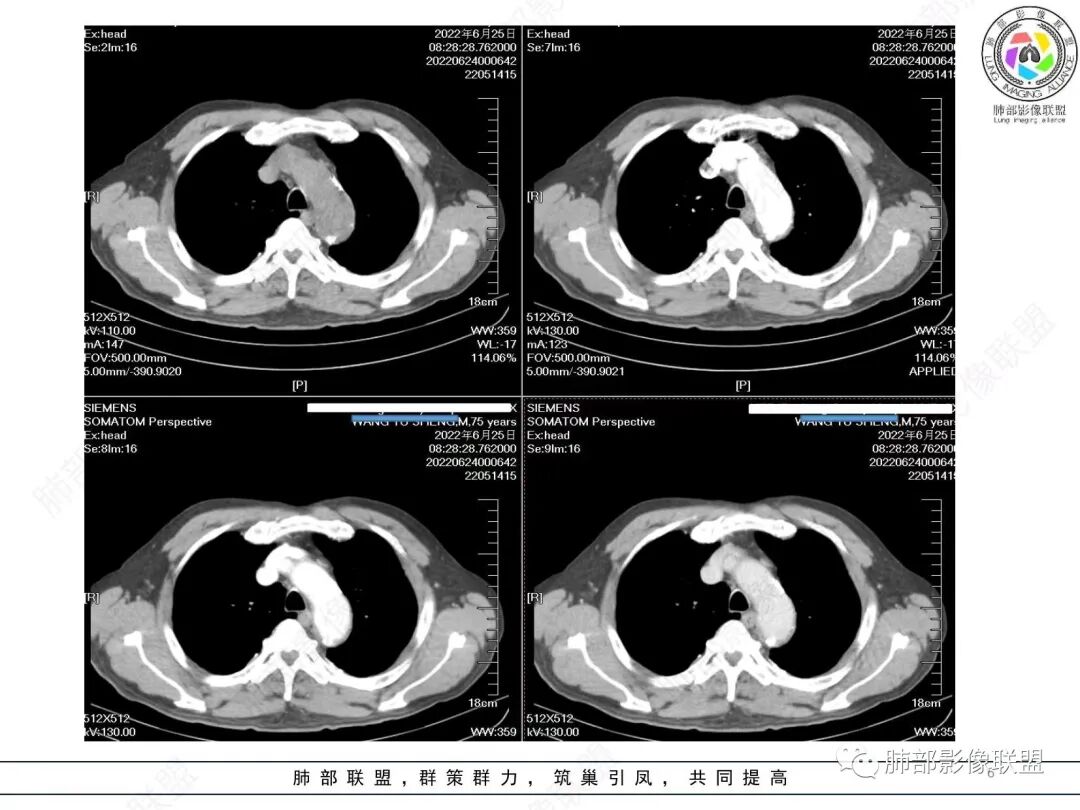

左肺上叶大肿块,膨胀性生长,边界清,密度较低,见部分坏死区,强化弱,肿块见支气管充气V扩张征,分布僵直,枯树枝特点,另一个重要特点血管造影征,淋巴瘤,肿块长轴与胸膜平行,与隐球菌鉴别,隐球荚膜抗原检查,明确诊断经皮肺穿刺。另胸膜钙化(问诊既往有无患胸膜炎病史)。

老年男性,糖尿病病史,消瘦、乏力三个月,影像表现左肺上叶胸膜下团块,有一定张力,内部疏松,可见支气管影及坏死区,增强病灶边缘环形强化,内部未见强化,考虑炎性肉芽肿病变,隐球?奴卡?放线菌?鉴别淋巴瘤。

左肺上叶胸膜下肿块,宽基底与胸膜相连,跨叶裂,边缘清晰膨隆,其内支气管充气,部分扩张、僵直,无明显强化,血管造影征,考虑淋巴瘤,鉴别腺癌

左肺胸膜下巨大占位,跨叶裂,宽基底与胸膜相连,胸膜钙化,平扫密度较低,强化不明显,可见内部血管显影,支气管充气征和扩张,考虑为恶性,倾向于淋巴瘤

增强没有强化,血管束正常,气管束有正常有扩张,内有空洞,考虑炎性病变,隐球?

左侧胸腔巨大肿块,跨叶生长,临近胸膜钙化,边缘模糊,可见支气管影,定位肺内,增强后轻度强化,边缘见血管影,考虑淋巴瘤,鉴别肉瘤

左肺上叶胸膜下肿块,膨胀性生长,边界清晰,密度不均部分坏死,未见强化,病灶内支气管迂曲扩张,病灶长轴与胸膜平行,胸膜下脂肪间隙存在,胸膜钙化,考虑放线菌?毛霉?鉴别淋巴瘤

支持淋巴瘤,左上肺大肿块,有分叶,边缘光整,病灶内密度不均,可见支气管扩张征,增强后可见血管影征。周围肺野清晰。

左肺上叶肿块,宽基底与胸膜相连,跨叶裂,边缘清晰膨隆,可见小分叶,其内支气管充气,部分扩张、僵直,呈枯枝征,支气管达边征,增强无明显强化,可见血管造影征,考虑恶性病变,淋巴瘤,鉴别粘液腺癌。

左肺团块样病灶,分叶,膨隆,不规则空洞,支气管枯枝样,血管造影征,考虑恶性,腺癌(肺肠型)。

我再建一下血管。支气管进入,但是近端推移,堵塞

大肿块,边缘光滑,深分叶

近端支气管堵塞、推移为主

部分类似于脐凹征

内部支气管扩张

肺动脉推移为主,边缘部分进入

大肿块、表面光滑但深分叶,肺门侧支气管堵塞

回头看,内部支气管近端其实不连续,伴随肺动脉不存在

这两点就不符合

1)部位:周围型或中央型软组织肿块,以周围型为多见,且肿瘤多位于肺上叶。如本例:该肿瘤位于左肺上叶。

2)大小及形态:由于本病恶性程度高,早期症状不明显,发现时肿块均较大。如本例病变巨大。

3)肿块边界和边缘:多较清楚,呈圆形、类圆形,且由于肿块生长速度不均匀,可见分叶,毛刺少见。有报道肿块周围毛玻璃影是多形性癌特征表现。

4)密度:肿块平扫为软组织密度,由于体积较大,内部常见大片状坏死,可出现不规则厚壁空洞或坏死内多发无壁小空洞,坏死多不均匀:坏死灶内可见如柳絮样的斑片样强化灶,坏死边缘与非坏死区分界不清本例坏死较明显,密度不均匀。

5)肿瘤强化方式:肺部恶性肿瘤强化程度与其血供丰富程度相关,血供丰富多强化明显,反之则较差。由于PSC 周边实性部分富血供及内部黏液变性、坏死,增强后肿块多数呈轻-中度边缘环形强化或不均匀小斑片状强化。国外学者对照病理发现肿瘤细胞或胶原组织增强扫描时强化,无强化的低密度区代表了黏液样变性区和出血坏死区。